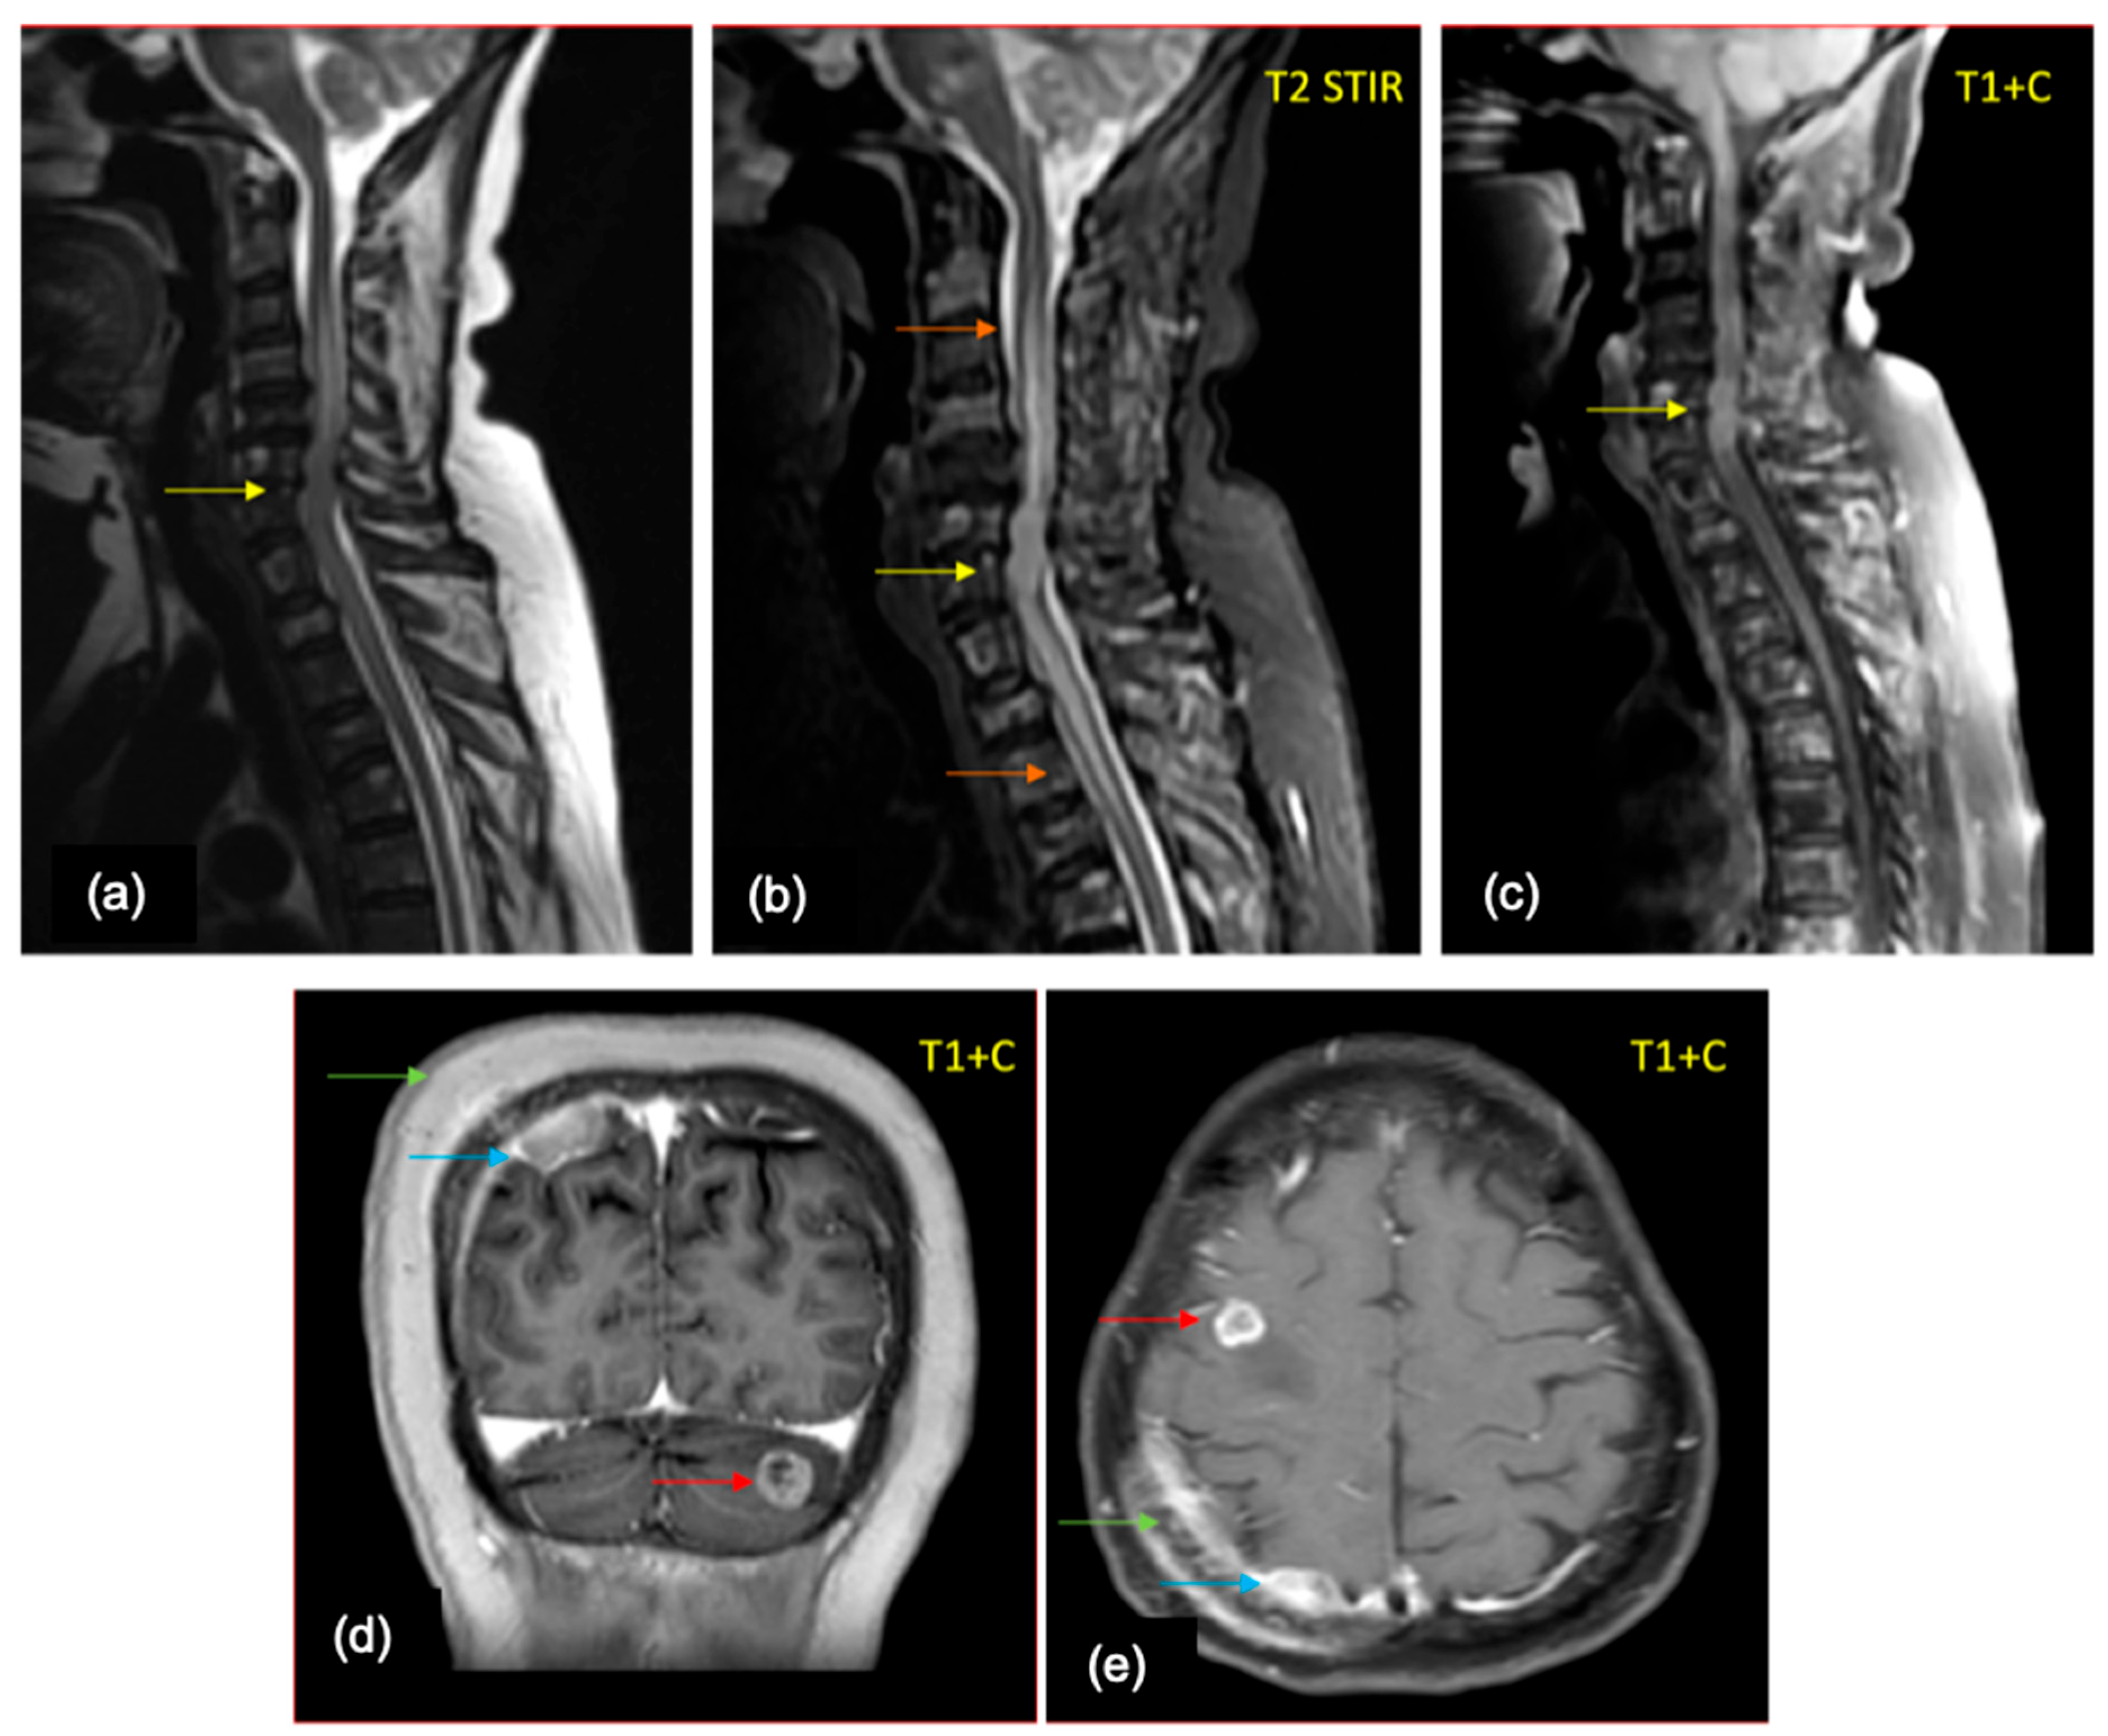

8. Spine Imaging

9. Etiopathogenesis

10. Presentation

11. Imaging Findings

12. Work-Up

13. Management

14. Conclusions